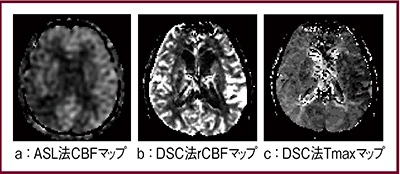

右中大脳動脈高度狭窄症例(70歳,女性)について,DSC法とASL法の画像を比較した(図4)。ASL法のpCASLでは右中大脳動脈はやや低信号で,CBFマップ(図4a)でも同様の所見が認められるが,DSC法のrCBFマップ(図4b)では左右差はほとんど見られず,虚血領域が不明瞭である。DSC法のTmaxマップ(図4c)では右が高信号となっており,ischemic penumbraを示唆する所見である。そこで,脳虚血におけるASL法とDSC法の各種パラメータを比較してみると,CBFとCBVは相関せず,ASL法と最も相関するのはDSC法のTmaxであった。この結果から,ASL法のCBFは,DSC法のTmaxの代替指標となりうると言える。

図4 脳虚血におけるASL法とDSC法の比較

pCASL画像とDSC各種パラメータマップ